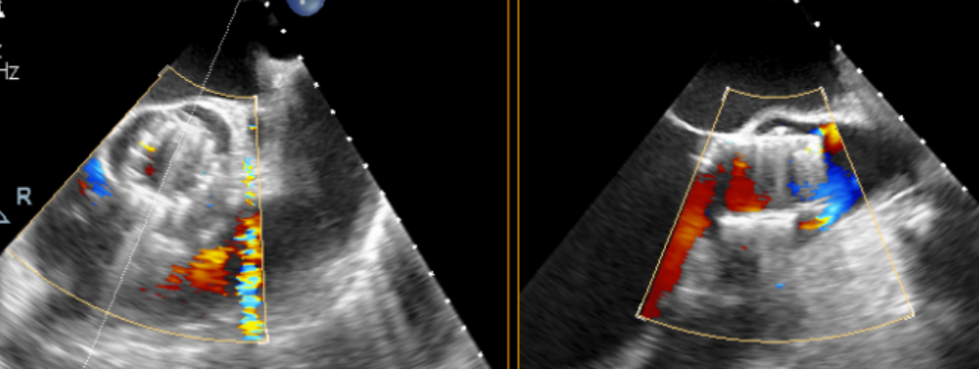

术前超声

术后超声

术中回顾及效果

手术过程顺利。术中通过右窦居中造影、定位件入窦造影及释放后功能确认等关键步骤,确保瓣膜锚定准确。器械用时约10分钟。术后即刻主动脉瓣反流程度由术前大量转为消失,术后主动脉瓣跨瓣压差5mmHg,血流动力学良好。